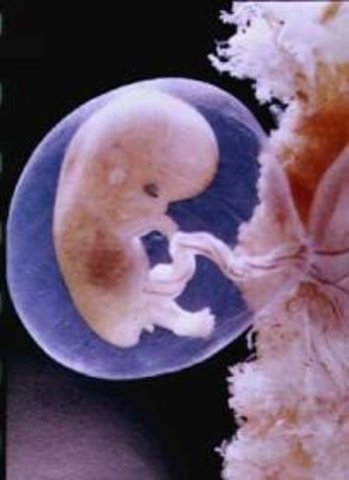

Comienza la formación del saco amniótico. El embrión crece hasta alcanzar 1,5 milímetros. el futuro embrión está formado por dos esferas huecas, una ubicada en el interior de la otra. La externa y más voluminosa, se llama saco coriónico. La interna incluye al llamado disco embrionario, el cual está formado por dos capas de tejido, por esto se lo denomina disco embrionario bilaminar.

El embrión adopta una forma simétrica, posee vasos sanguíneos propios y comienza a formarse el corazón. Crece hasta 2,5 milímetros.

En el embrión se ha formado el corazón y comienza a latir. Se trata de un corazón primario el cual aún no está dividido en ventrículos.

El sistema nervioso central comienza a desarrollarse. El embrión mide de 3 a 4 milímetros

El embrión se muestra en forma de C. La cabeza destaca a simple vista. Ojos y orejas comienzan a formarse. El corazón comienza a desarrollar sus válvulas y tabiques. Empieza la formación de órganos digestivos.